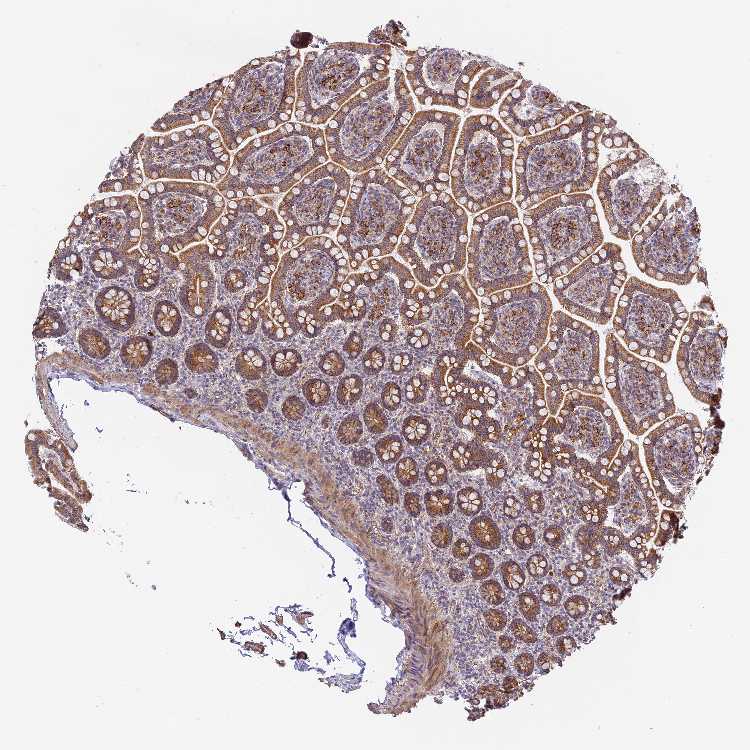

SMALL INTESTINE - Antibody stainingi

Antibody staining in the annotated cell types in the current human tissue is reported as not detected, low, medium, or high, based on conventional immunohistochemistry profiling in selected tissues. This score is based on the combination of the staining intensity and fraction of stained cells.

Each image is clickable and will lead to virtual microscopy that enables deeper exploration of all samples and also displays staining intensity scores, fraction scores and subcellular localization as well as patient and tissue information for each sample.

Antibody HPA044425

Glandular cells High